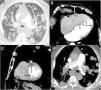

Our patient was an 87-year-old man, former smoker with a history of anticoagulated atrial fibrillation who underwent surgery for a malignant SFTP. Two years after surgery, a follow-up computed tomography (CT) scan of the chest revealed multiple bilateral pulmonary nodules compatible with metastases (Fig. 1A). CT-guided core needle biopsy confirmed that the pulmonary nodules were consistent with SFTP metastases. In the CT follow-up 1 month later, the pulmonary lesions had grown rapidly, and several nodular lesions were observed in the chambers of the heart, highly suggestive of cardiac metastases (Fig. 1B, C). A few days after the last CT follow-up, the patient was diagnosed with a massive bilateral pulmonary thromboembolism (Fig. 1D) and died a few hours later.

(A) Axial CT image of the chest (lung parenchyma window), showing multiple bilateral pulmonary nodules. (B and C) Axial (B) and sagittal (C) chest CT images (mediastinal window) showing several nodules in the right ventricular free wall (white arrow), interventricular septum (short black arrows) and left ventricular free wall (long black arrow). (D) Axial CT image of the chest (mediastinum window) showing filling defects in the pulmonary arteries (arrows).

Cardiac metastasis in SFTP is exceptional, and we have only found 1 documented case of left atrium metastasis by intracavitary extension from the left upper pulmonary vein. In our case, the rapid and extensive involvement of several chambers of the heart (coinciding with accelerated pulmonary progression) suggests a previously unreported hematogenous spread of the tumor. Although we were unable to confirm cardiac involvement with histology in our patient, we believe that imaging tests and rapid pulmonary progression (confirmed pathologically) reinforce the hypothesis of a metastatic origin of the cardiac lesions. We also believe that the subsequent pulmonary thromboembolism could be associated with tumor infiltration of the right heart chambers.